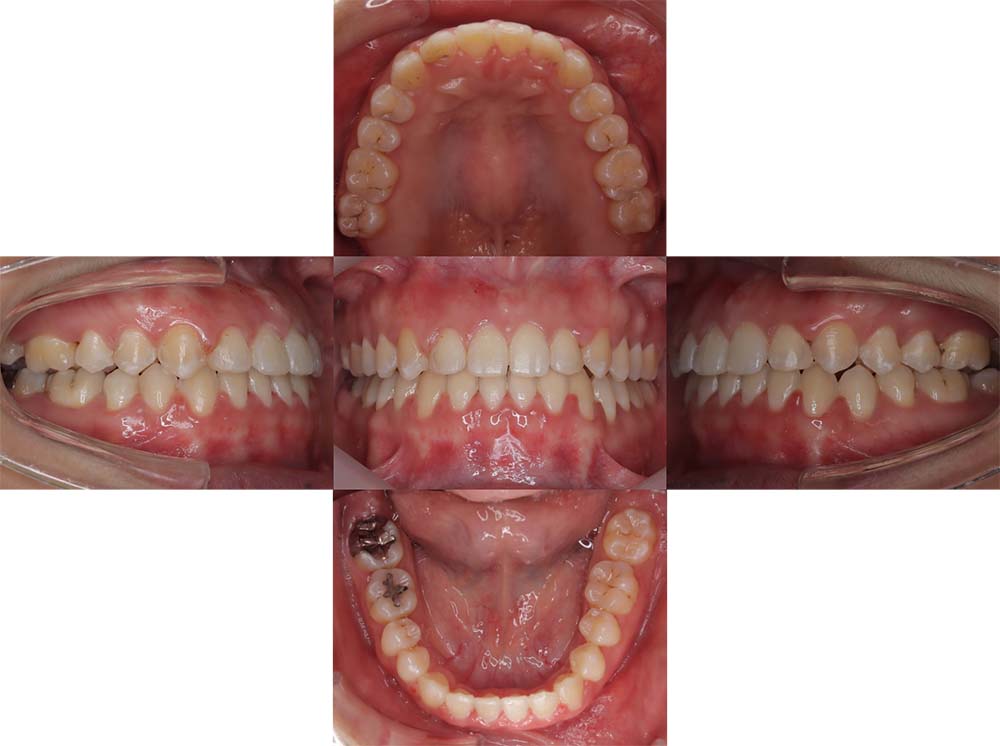

症例03

| 主訴 | 歯並びがガタガタしている。 |

| 診断名あるいは主な症状 | 過蓋咬合、叢生 |

| 年齢/性別 | 26歳・女性 |

| 矯正ステージ | 大人の矯正治療 |

| 治療方法 |

ワイヤー矯正 歯科矯正用アンカースクリュー(3本) |

| 抜歯部位/抜歯有無 | 抜歯 |

| 治療内容 | 上下顎の奥歯を後方に移動後、ガタガタの改善と上下顎前歯を後退させた。 |

| 費用 |

90万円程度(2025.10時点の料金となります。) ※矯正基本料金、アンカースクリュー、審美ブラケットを含む |

| 治療期間 | 2年8ヶ月 |

| 主なリスク・副作用 | 痛み、歯根吸収、歯肉退縮、虫歯、後戻り |